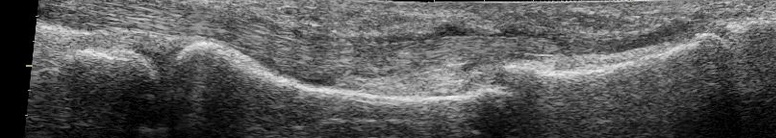

Hallazgos ecográficos

Ecografía portátil: Pérdida ósea de la cortical en falange distal del dedo afecto (segundo de la mano derecha).